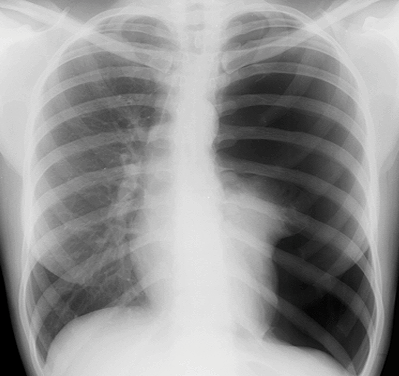

A 33 year old G2P1 female at 32 weeks GA presents with blunt trauma following an MVC. She will be hypotensive due to both hypovolemic shock from a pelvic fracture and obstructive shock from a tension pneumothorax. Fetal monitoring will show the fetus in distress with tachycardia and late decelerations. Early airway intervention should be employed, with thoughtful selection of drugs for sedation and paralysis given the pregnancy. After intubation, the patient will remain hypotensive. She will require massive transfusion and coordination of care between orthopedics, general surgery, and obstetrics. The patient’s husband will also arrive after intubation and the team must give him the bad news.

CXR for the case found here:

(CXR source: http://cdem.phpwebhosting.com/ssm/pulm/pneumothorax/images/cxr_ptx_3.png)